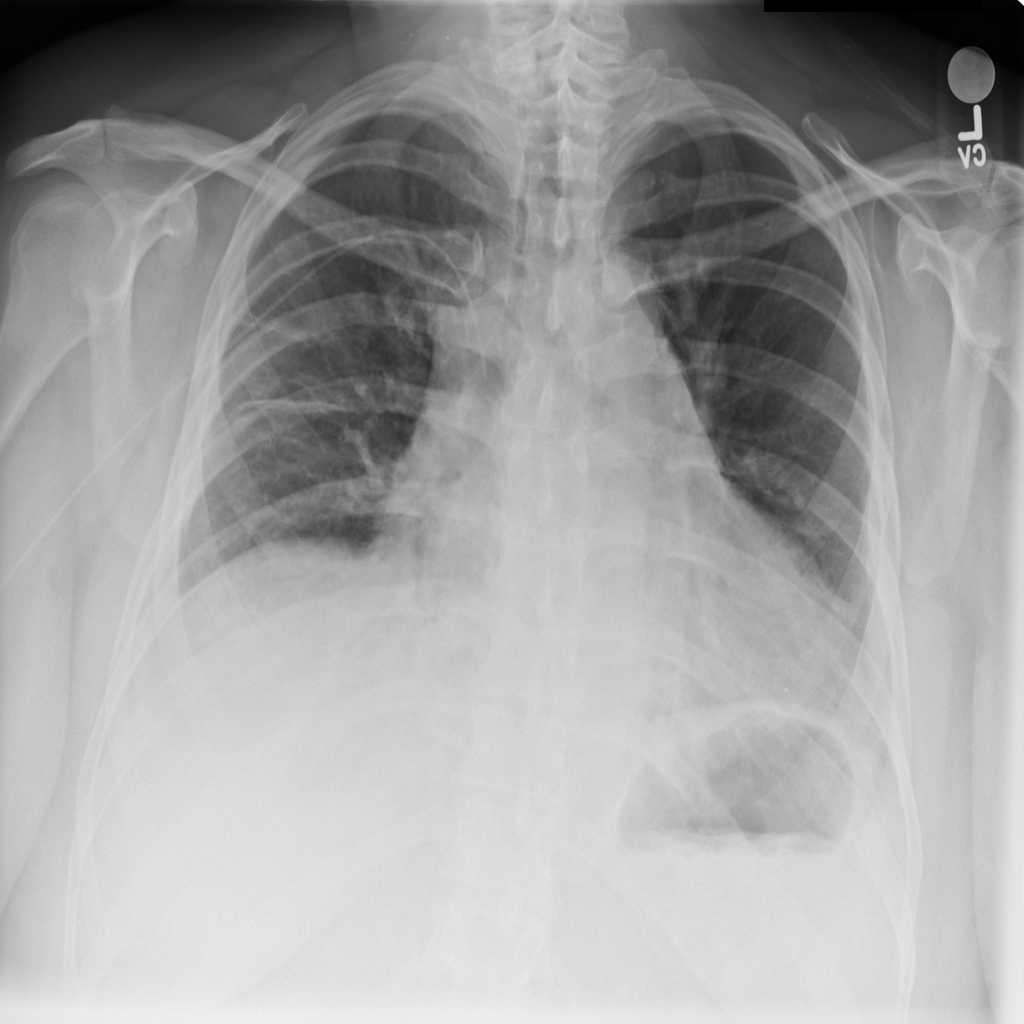

PAT-DB80 · IMG-001Atelectasis

PAT-DB80 · IMG-001

PA